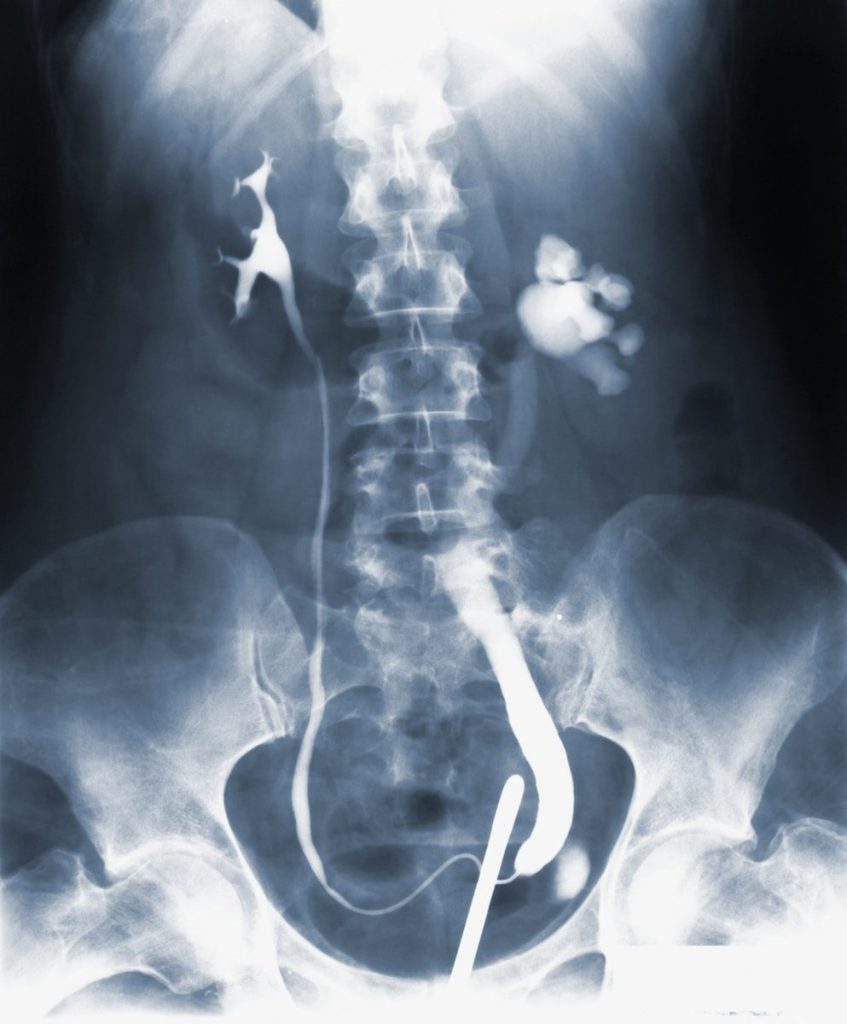

Lithiase urinaire

Calculs rénaux très fréquents. Lithotripsie extracorporelle (LEOC), urétéroscopie au laser, néphrolithotomie percutanée. Récidive fréquente, suivi long terme.